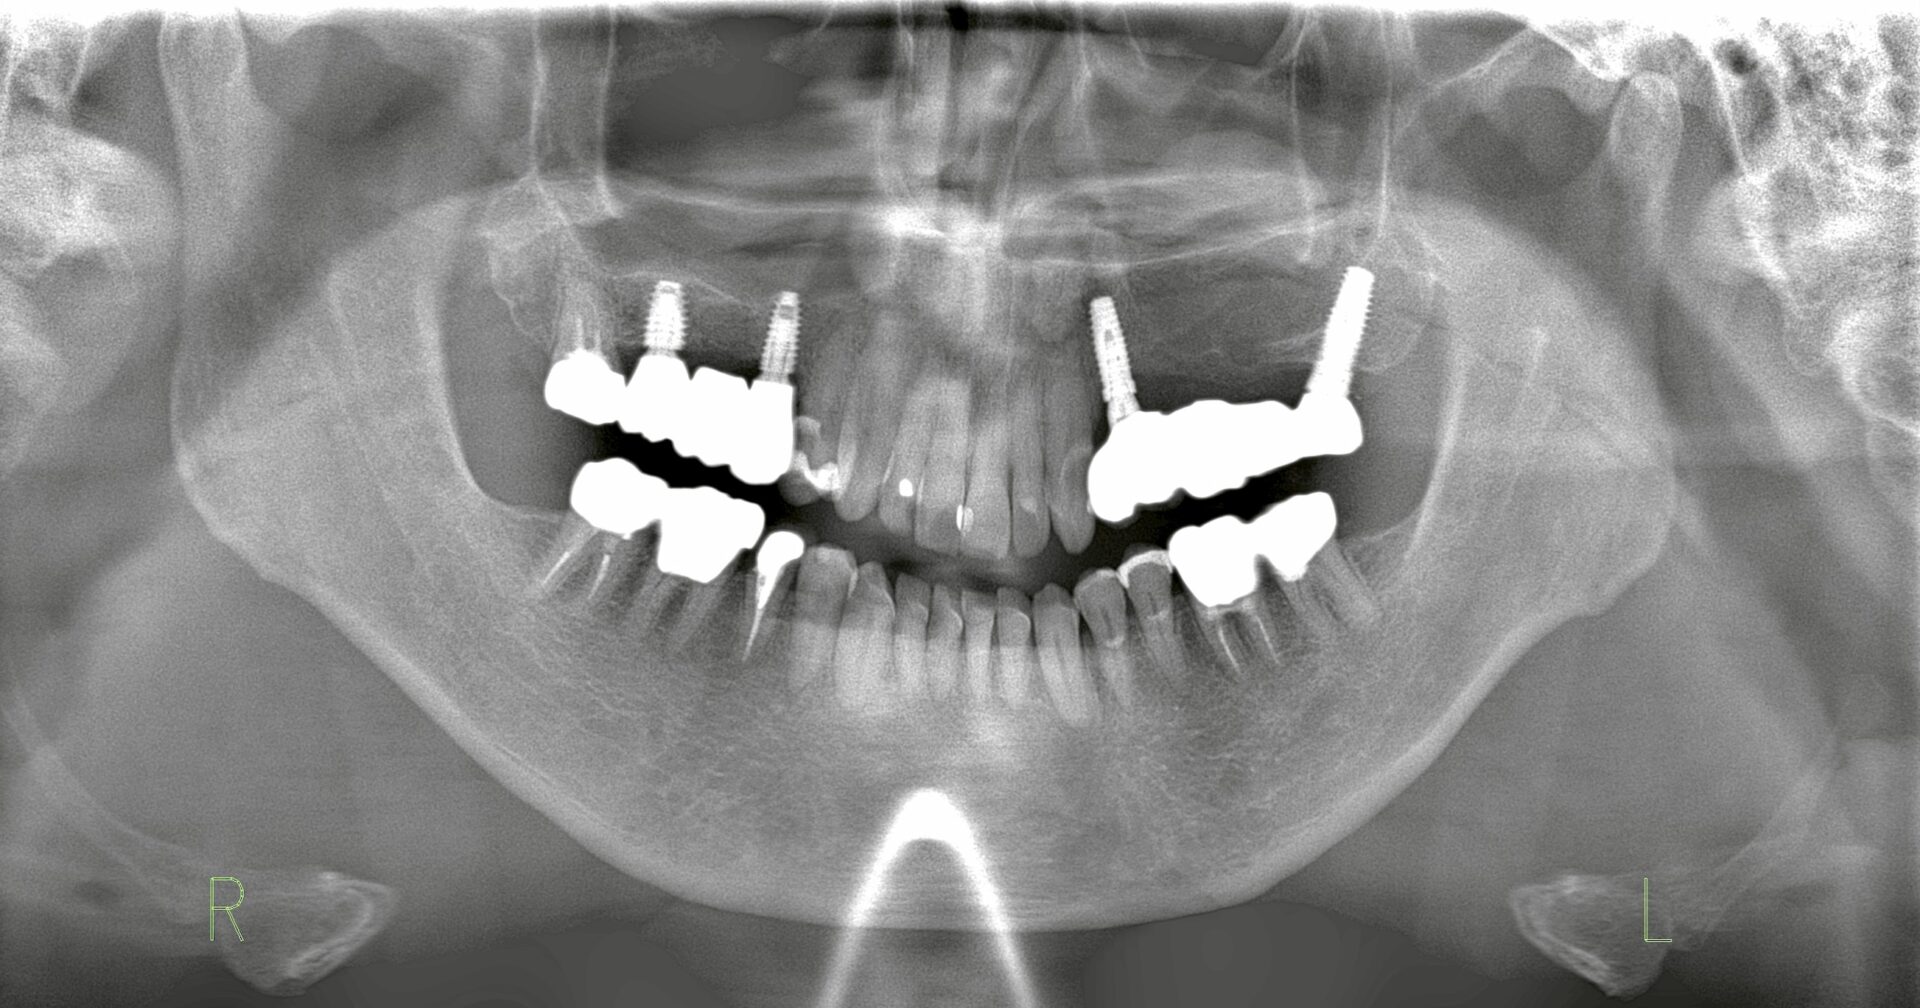

| インプラント後レントゲン写真 | ![]() |

| Consideration | 右上ブリッジは、歯根破折を認めるため抜歯を行った。その後骨の回復を待ってからインプラント治療を計画したが、上顎洞までの距離が短くサイナスリフトの必要性があった。既存骨は4mm認めるためサイナスリフトと並行し同時埋入を行った。5ヶ月の待機期間を経てブリッジ補綴へ。サイナスリフトはクレスタルアプローチテクニックで実施した。 |